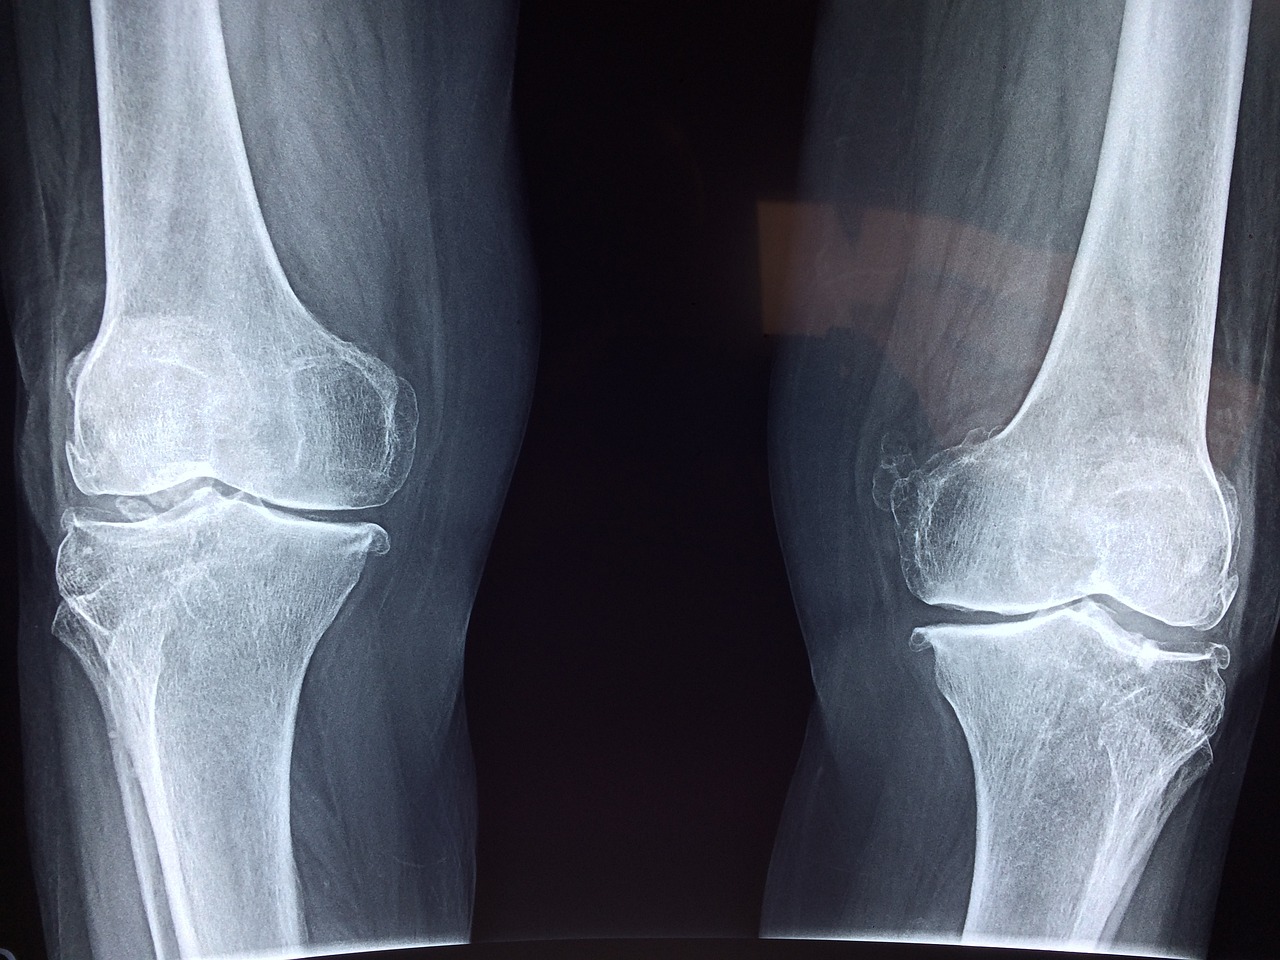

나이가 들면 자연스럽게 무릎 통증이 찾아오고, 심할 경우 인공관절 수술을 받아야 하는 상황이 생기곤 합니다.

무릎 인공관절 수술은 평균적으로 한쪽 무릎 기준 300만 원 이상의 비용이 들 수 있습니다.

- 건강보험 기준 ‘인공관절치환술(슬관절)’ 필요 질환자

※ 병원 진단서 등 '슬관절 인공관절이 필요한 상태'임을 증명할 수 있어야 합니다.

무릎 인공관절 수술은 고통을 줄이고 삶의 질을 크게 향상시키는 치료입니다.